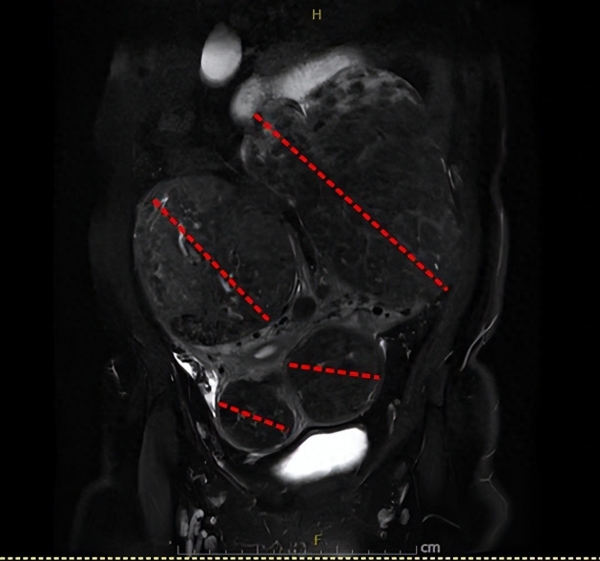

最大的肌瘤跟柚子差不多大小。

42岁的曹女士家住青山,最近三个月她的体重直线上升,肚子也变得越来越大,像六七个月的孕妇一样,还伴有反复出血,但每次持续两三天就好了,她也没有太在意。在家人的催促下,8月22日曹女士前往家附近的社区卫生服务中心检查,B超提示腹部有两个巨型包块。为进一步明确病情,第二天一早她来到武汉科技大学附属普仁医院妇科门诊看诊。经过详细检查,医生发现曹女士的子宫内不仅存在多发肌瘤,而且肌瘤体积惊人,其中两个竟然有柚子大小。由于曹女士血糖不稳,手术存在一定的风险。